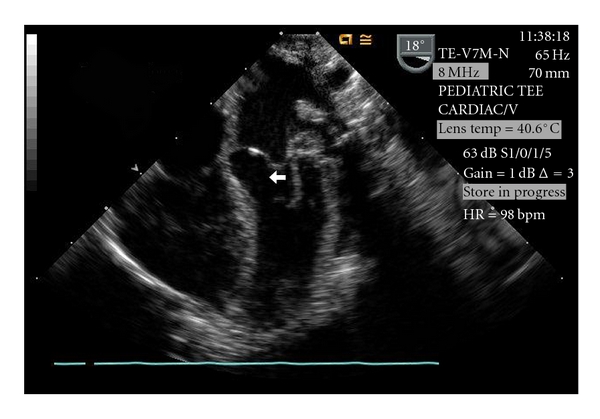

Dissecting ventricular septal hematoma (DVSH) rarely occurs after repair of a ventricular septal defect (VSD) but can lead to serious complications such as septal rupture, myocardial rupture, cardiogenic shock, heart block, outflow obstruction, cardiac tamponade, abscess transformation, and death. This paper describes the diagnosis and management of acute, severe, left ventricular outflow tract obstruction caused by the development of a DVSH after VSD repair.